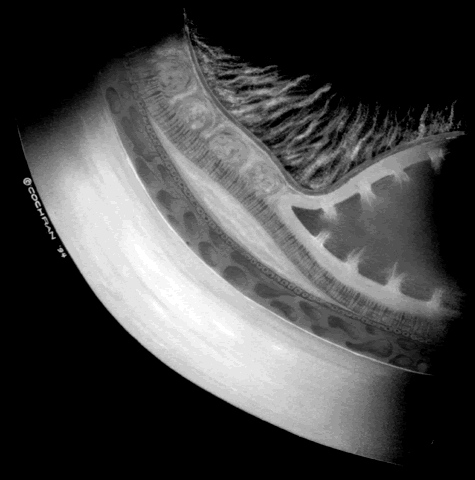

ROP accounts for a large number of retinal detachments in the pediatric population. The International Classification of Retinopathy of Prematurity helped greatly to improve communication about, and consequently treatment of, ROP. It describes affected eyes in terms of stage, zone, and absence or presence of plus disease18 (Figs. 1, 2, and 3). Screening of premature infants is an important feature in the care of ROP, which is perhaps the most significant and enduring finding of the Cryotherapy for Retinopathy of Prematurity Study (Cryo-ROP Study).19

Fig. 2. Standard zoning patterns of retinopathy of prematurity. Zone 1 is defined as a circle with a radius of two times the distance between the center of the optic nerve and the foveola. Zone 2 is a circle whose radius is from the center of the optic nerve to the nasal horizontal ora serrata. All the remaining area of retina is zone 3.